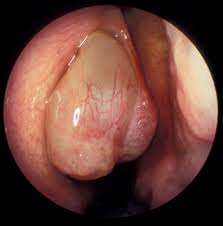

They are insensitive to pain but produce symptoms of nasal blockage and loss of sense of smell and may be. These growths are often shaped like teardrops and form in groups. Info about nasal polyps, cause and treatment of nasal polyps, homeopathic remedies and homeopathy treatment for nasal polyps. Nasal polyps grow in inflamed tissue of the nasal mucosa. Unfortunately, quitting smoking often does not reverse the symptoms since permanent damage has been done to the nose.

In general, the negative impact of polyps on a patient's health relates to the sinus and nasal symptoms as well as overall negative impact on quality of life. Symptoms are due to the size and location of the polyps and associated mucosal inflammation; Some of the symptoms of nasal polyps are difficulty in breathing, poor sense of smelling, continuous discharge of fluid from the nose, stiffness in the nose and face and frequent sinus infection that do not respond to drugs. They include nasal congestion and blockage, rhinorrhea, posterior nasal drip, and decreased sense of smell. The most common symptoms they cause are a stuffy, runny nose. Small nasal polyps may cause no symptoms. Symptoms of colon polyps include rectal bleeding. They line the inside of your nose or your sinuses. Most of them are noncancerous, and doctors can usually tell these apart from cancer, though more extensive testing usually stomach polyps don't show any symptoms. Nasal polyps develops as a result of chronic inflammation in body and associated with health issues like allergies, asthma etc. Nasal polyps (np) are noncancerous growths within the nose or sinuses. The secretions are dry and the turbinates are whitish. Nasal polyps can be described as anomalous growth of inner lining of nasal airway or even sinuses.

Small nasal polyps may cause no symptoms. 8 colon polyps symptoms, pictures, types, causes, treatment. Larger growths or groups of nasal polyps can block your nasal passages or lead to breathing problems, a nasal polyps themselves are soft and lack sensation, so if they're small, you may not be aware you have them. Sometimes they grow large, though, and when they do they can develop ulcers. Nasal polyps are noncancerous growths of the tissues that line the nose and sinuses. Find out about nasal polyps, which are painless soft growths inside your nose. It is important to distinguish nasal polyps from neoplastic lesions, particularly if symptoms are. They are not dangerous, but they should still be treated for the patient's comfort at least if they do cause discomfort. Nasal polyps develops as a result of chronic inflammation in body and associated with health issues like allergies, asthma etc. A nasal polyp is a mass of gelatinous tissue which usually forms from allergy. Symptoms are due to the size and location of the polyps and associated mucosal inflammation; They are also usually triggered by chronic inflammation and are associated with a number of health conditions. Symptoms include trouble breathing through the nose, loss of smell, decreased taste, post nasal drip, and a runny nose.

Symptoms include trouble breathing through the nose, loss of smell, decreased taste, post nasal drip, and a runny nose. A nasal polyp is a mass of gelatinous tissue which usually forms from allergy. These are fleshy growths that arise from the small cavities (sinuses) or the lining of the nose. Nasal polyps (np) are noncancerous growths within the nose or sinuses. They usually occur in both the right and left nasal passages and can block the flow of air.